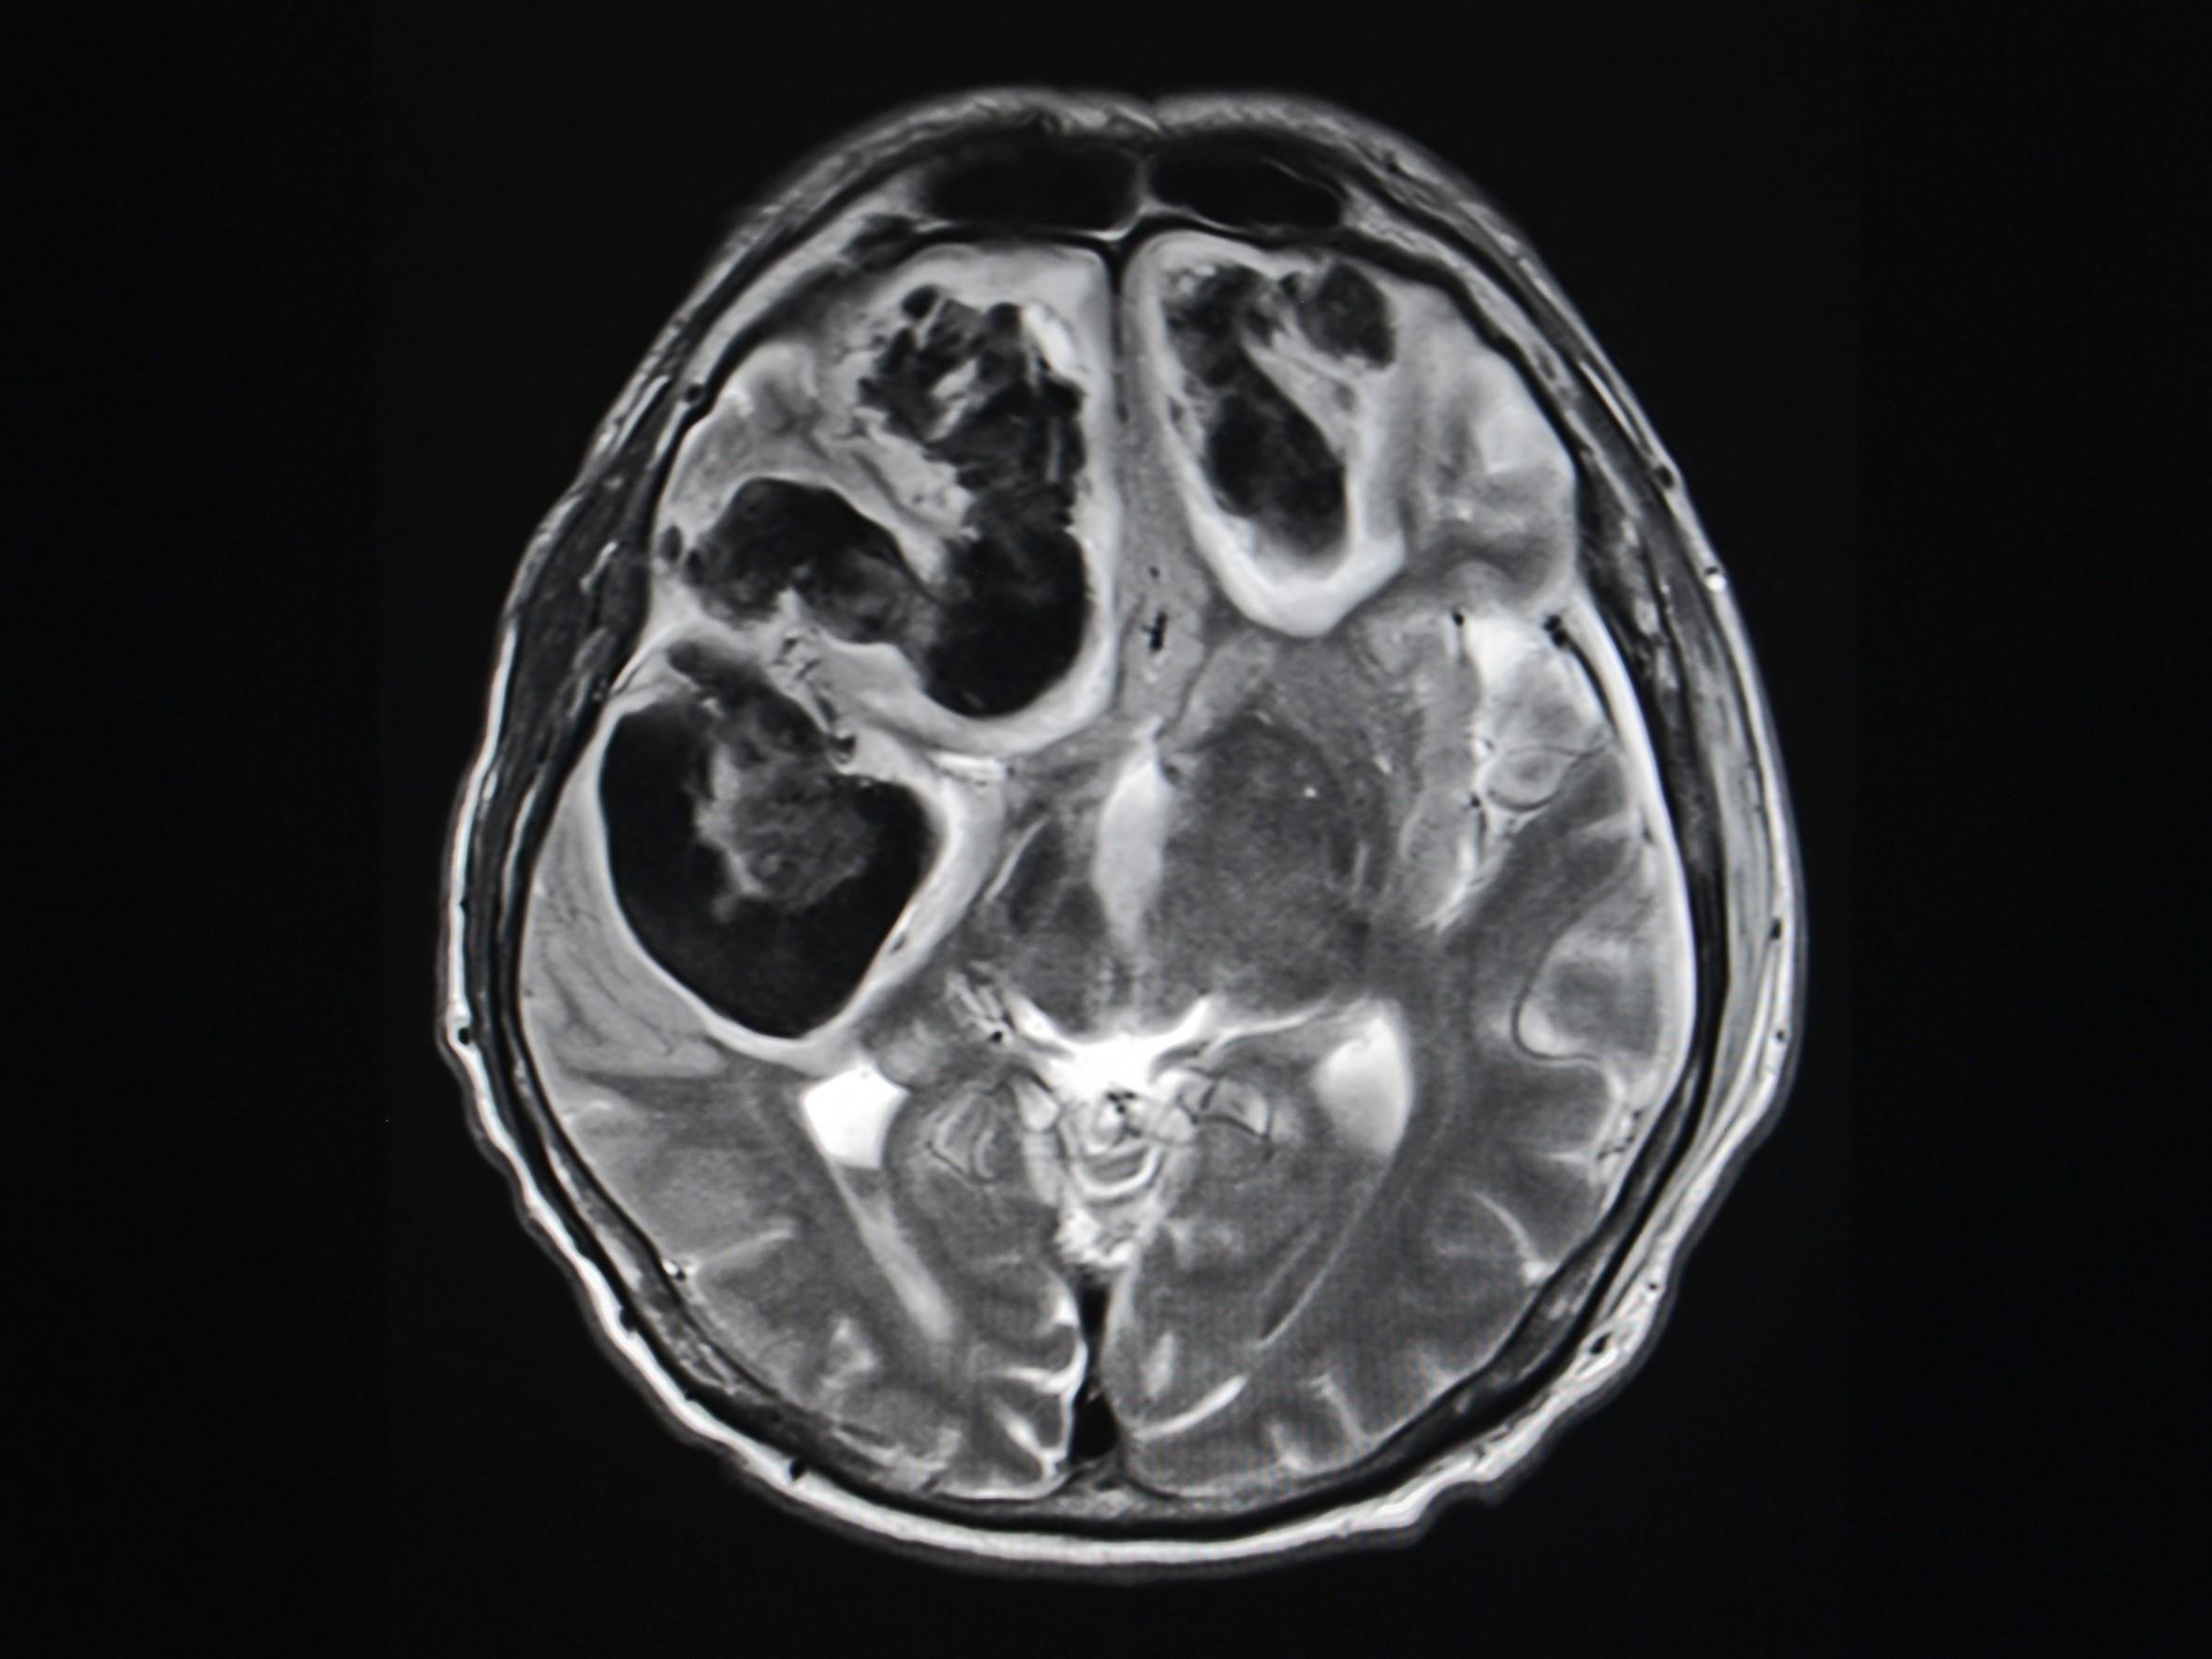

Stroke is a very complex mental condition. There can be numberless reasons leading to a stroke. Some of the major factors are explained below here